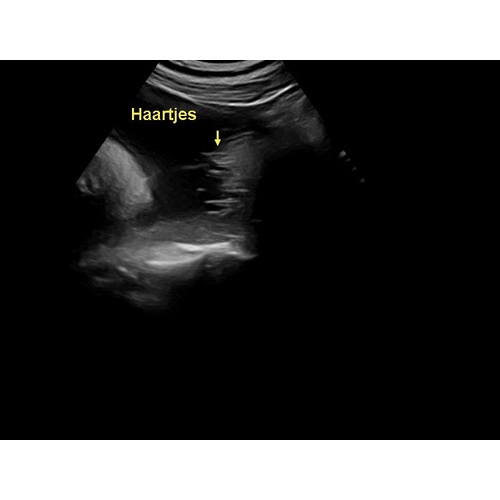

Zeker! Bij ons werd van 30 weken bij de echo's gezegd dat hij een hele bos haar had en dat heeft hij inderdaad ook 😄

Dat kan😄 was bij ons goed te zien

Ja zeker! Was bij ons goed te zien

Ja bij mijn meisje zagen ze een paar plukjes bij de oren🥰

Ja, zowel bij de echo van 24W en 28W was het allebei goed te zien 😊 dus ben eens benieuwd!

Ja ons meisje laat op de echo steeds een wapperend bosje haar zien in t water😍

ja bij ons vanaf 30 weken te zien, ze is ook geboren met een flinke bos haar!

Ja hoor, hier was een duidelijke bos haar te zien haha.

Ja zeker! Dit was met 29 weken. Veel haar kregen wij te horen 😃

Wij kregen ook te horen dat het een bos haar heeft, echo van 34 weken 😊

Bij mij zagen ze haartjes bij de 33 weken groeiecho. 🤗